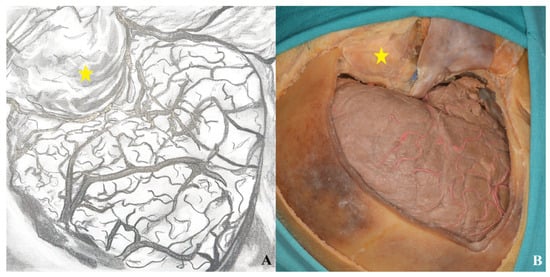

3.1.5. Dura Incision

3.3. Lamina Terminalis